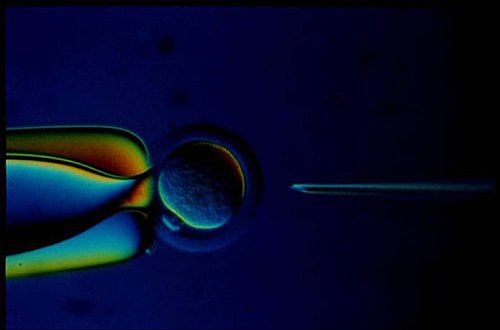

所謂試管嬰兒,就是經由『體外受精-胚胎植入』的過程,將母親的卵子取出在培養基培養,加入父親的精虫待受精分裂成2-8個細胞的胚胎再植回母體子宮內,著床。而在體外培養皿的時間約48-72小時,甚至到120小時之囊胚期,故出生的嬰兒,稱為試管嬰兒。而今40歲以下病患成功率可達40%以上!

(5)取卵時全身鎮靜處置,由陰道超音波指引下取卵從濾泡中抽出濾泡液在解剖顯微鏡下將卵子找出,並判斷其成熟度,放入培養基置於37℃ 溫箱培養。

(6)成熟的卵子培養2-6小時,可加精子,而不成熟的卵子需較長時間培養,精子需先加以處理,經洗精再挑選活動力好的精子,一顆卵子僅需10萬到15萬的精子就足以受精了。